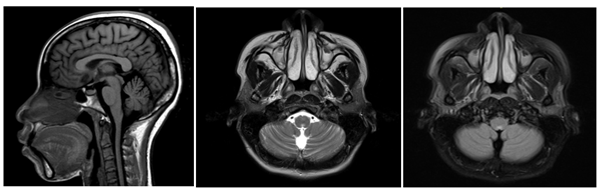

Debido a la evolución tórpida de la paciente, su familia fue interrogada sobre el estado de la paciente, a lo que el familiar agregó síntomas adicionales consistentes en episodios de accesos de tos con posterior alteración de la conciencia y movimientos anormales en las extremidades compatibles con crisis epiléptica tónica clónica bilateral con amnesia del evento. Se sospechó una etiología en el sistema nervioso central por lo que, posteriormente, se solicitó una resonancia magnética contrastada del cerebro; esta reportó una lesión única hiperintensa en la secuencia T2 en el área postrema; por lo tanto, se enfocó como un posible SAP (Imagen 1). Para descartar posibles etiologías se realizó una punción lumbar que informó presión de apertura de 26 cmH2O, 1 linfocito, glucosa 56mg/dL, proteínas 26 mg/dL; Gram/Tinta china/Panel molecular para meningitis fueron negativos. Además, los cultivos para bacterias, hongos, micobacterias, PCR-RT para tuberculosis y bandas oligoclonales fueron todos negativos. Dado lo anterior, se decidió cambiar el esteroide de prednisolona a hidrocortisona 100 mg cada 8 horas. La paciente mejoró significativamente después de este ajuste hasta el punto en que sus síntomas cesaron, y pudo ser dada de alta con una fórmula médica.

Imagen 1. A) RM del cerebro en corte sagital, en secuencia T1, donde no se observa hallazgo patológico evidente. B y C) RM del cerebro en plano axial en secuencias T2 y FLAIR, donde una lesión hiperintensa concéntrica se observa en el área postrema.

Imagen 1. D y E) RM del cerebro en plano axial, en secuencia T1, TRACE y ADC donde no se observa restricción a la difusión. F) RM del cerebro en el plano axial, secuencia T1 post contraste donde no se observa realce de la lesión descrita.